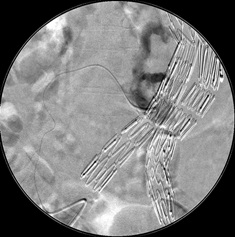

消化道出血栓塞(n-BCA)

腹腔 动脉造影发现造影剂外溢,但供血动脉似乎来自于胃十二指肠动脉,但不确定 |

超选择胃十二指肠动脉显示出血的动脉来自于胃十二指肠动脉的一个细小的未命名动脉分支 |

弹簧栓子阻塞胃十二指肠动脉后造影 |

选择性胰背动脉造影未发现明显出血 |